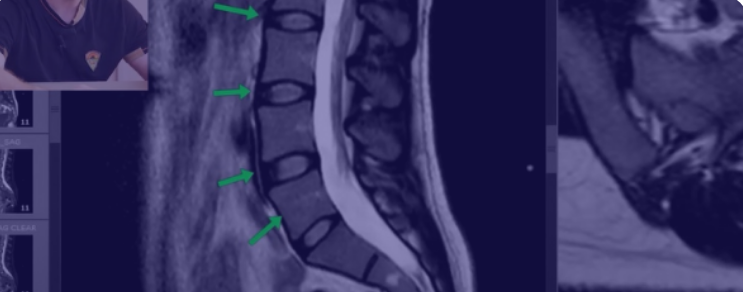

Видеоурок "Как читать МРТ поясницы", две части. Автор: Доктор Епифанов

На примере большого количества снимков вы узнаете, как выглядит грыжа, протрузия, стеноз канала, сдавление корешков, жировая дегенерация мышц, как мышцы спазмируются при грыже, откуда берется поясничный прострел и многое другое. Если вы будете постоянно смотреть МРТ своих пациентов и сравнивать снимки с жалобами, то сможете все глубже погружаться в понимание причины боли.